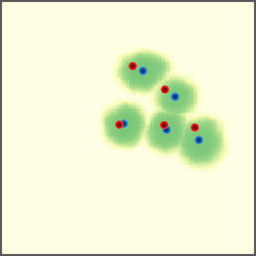

POI Selection. The first step of the proposed approach requires selecting a set of POIs to set up a point-to-point correspondence. In this experiment, we investigate different POI selection strategies. First, we investigate directly using landmarks as the POIs since they usually have strong semantic meaning and can be annotated before the intervention. Second, we also investigate an automatic solution that uses the Harris corners as the POIs to avoid the labor work of annotation. Finally, we try random POI selection.

As shown in Figure 7 (a), we find our approach is prone to overfitting when trained with landmark POIs. This is actually reasonable as each CBCT volume only contains about a dozen of landmarks, which in total is about 3,00030003,000 POIs. Considering the variety of the field of views of our dataset, this is far from enough and leads to the overfitting. For the Harris corners, a few hundreds of POIs are selected from each CBCT volume, and we can see an improvement in performance, but the overfitting still exists (Figure 7 (b)). We find the use of random POIs gives the best performance and generalizes well to unseen data (Figure 7 (c)). This seemly surprising observation is, in fact, reasonable as it forces the model to learn a more general way to extract features at a fine-grained level, instead of memorizing some feature points that may look different when projected from a different view.

Refer to caption

(a) landmark

(b) Harris corner

(c) random

Figure 7: Training and validation losses of different POI selection methods.